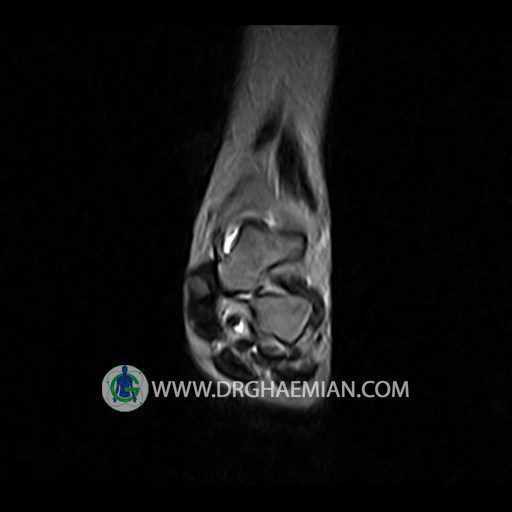

پزشکان اغلب از تصویربرداری ام آر آی برای تشخیص و درمان عارضه های پزشکی که فقط با استفاده از اشعه ایکس یا میدان مغناطیسی و امواج رادیویی قابل مشاهده است، استفاده می کنند. دستگاه ام آر آی تصاویر دقیق از ساختار های داخلی بدن ایجاد می کند. در این کیس تورم مچ پا بیمار مشاهده می شود.

گزارش پزشک :

LEFT KNEE MRI

(Without contrast)

Technique: Sagittal T1, T2 , Axial GE , coronal & sagital fatsat .